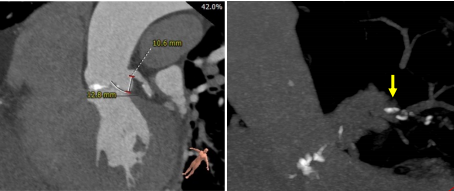

三叶式主动脉瓣,瓣环周长73.6mm,平均径22.5mm;瓦氏窦可;左冠开口高度11.3mm,右冠开口高度19.0mm。

弓部及入路评估

弓部角度及距离适宜,双侧入路走形略迂曲,内径适宜,少量钙化。